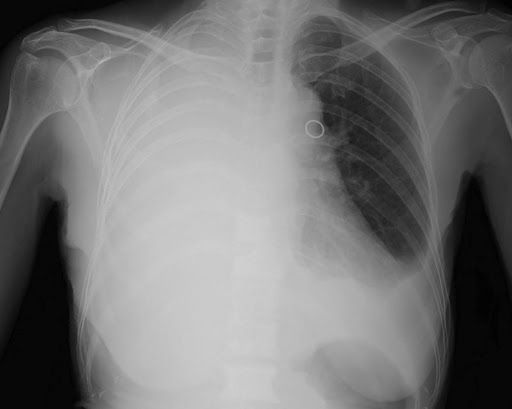

Exames essenciais antes da cirurgia torácica

Algumas avaliações são

indispensáveis

para que a equipe médica possa confirmar se há segurança para seguir com o procedimento:

Tomografia de tórax – fornece uma visão precisa da área a ser operada;

Espirometria – mede a capacidade respiratória e ajuda a planejar o pós-operatório;

Eletrocardiograma e ecocardiograma – avaliam como está o funcionamento do coração;

Exames de sangue – como hemograma, função renal e coagulograma.

Geralmente são solicitados tomografia de tórax, espirometria, eletrocardiograma, ecocardiograma e exames laboratoriais como hemograma, coagulograma e função renal.